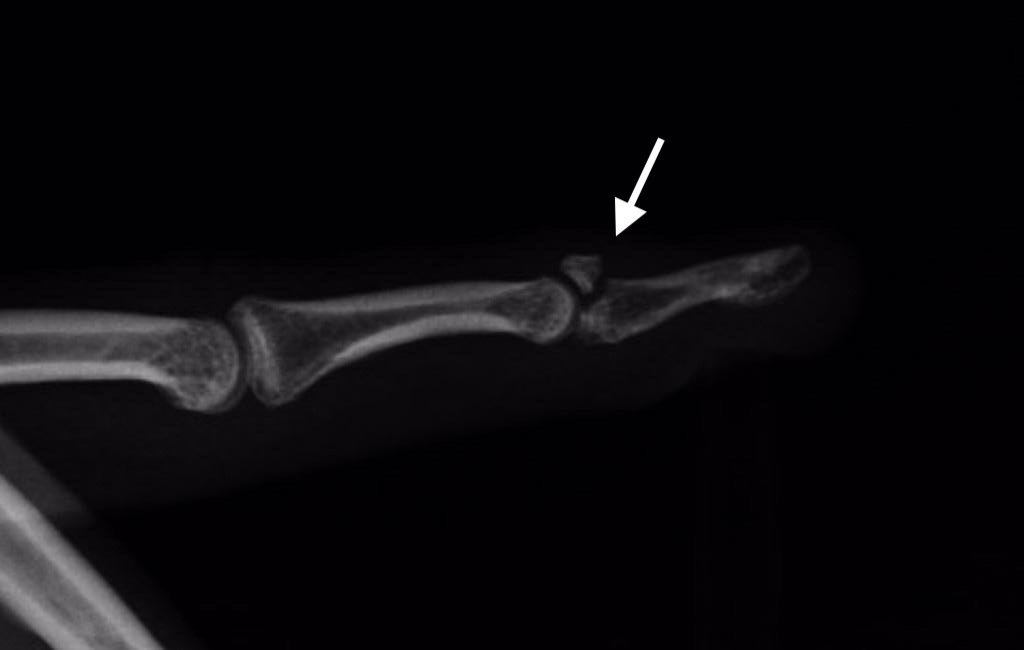

En algunos pacientes, la deformidad se debe a la rotura del tendón junto con un fragmento de hueso unido a él, en cuyo caso se habla de “fractura-arrancamiento”.  En estos casos, la deformidad será similar a cuando se rompe sólo el tendón (Figura 3).

Figura 4 - Radiografía de Fractura-avulsión del tendón extensor terminal (bony-mallet)

El dedo en martillo se diagnostica fundamentalmente mediante la exploración física del Cirujano de Mano.  Las radiografías simples son útiles para determinar la presencia de una fractura-avulsión (Figura 4).